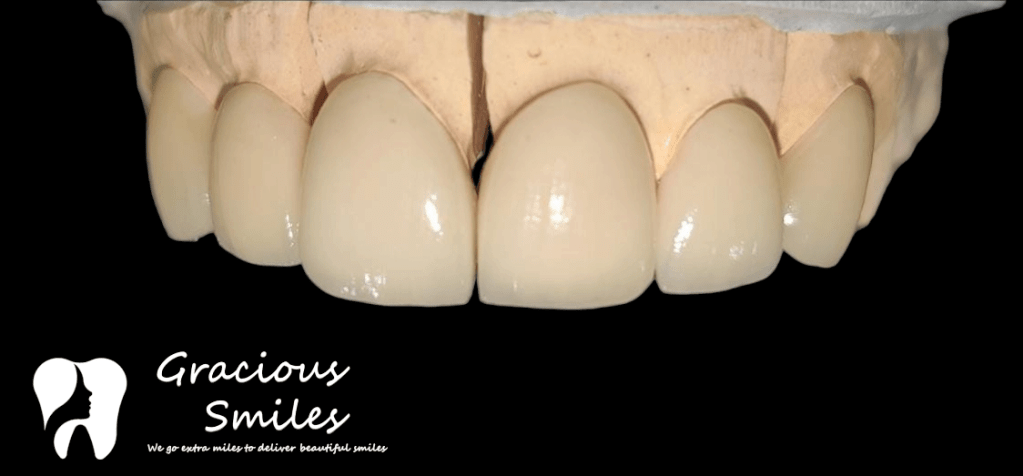

Ceramic Veneers